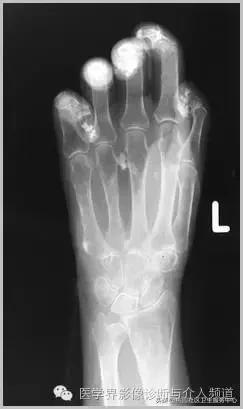

4、痛风石

为尿酸盐沉积形成,发生在关节周围软组织、包括韧带、肌腱、滑囊,眼、耳、鼻、喉、皮肤, 50%的钙化为X线平片可见。

痛风石,可见软组织肿胀及钙化灶。